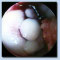

Am Schultergelenk werden die Operationen hauptsächlich arthroskopisch, d.h. über einen kleinen Hautstich wird eine Kamera eingeführt und über einen zweiten Stich werden die Instrumente eingeführt. Hierbei können dann neben Entfernung rheumatisch entzündeten Gewebes auch Knochensporne abgetragen werden (Bild 1 und 2 - Knochensporn am Schulterdach vorher - nachher), oder Kalk aus der schultersehnen entfernt werden ( Bild3) oder Riße der Muskel - Sehnenmanschette müssen vernäht werden ( Bild 5 Riß in der Schultersehene)